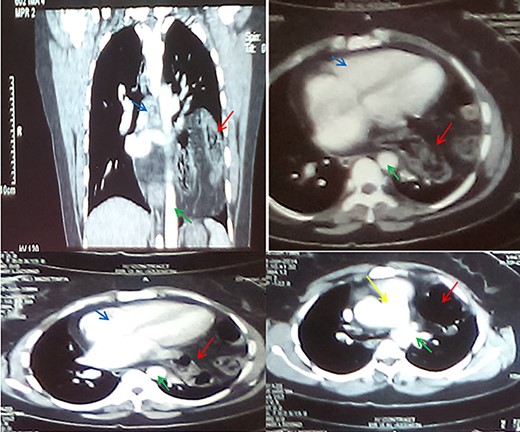

CT sections with contrast showing abdominal viscera in the thorax (red arrows), aorta (green arrow), the heart (blue arrows) and the pulmonary trunk (yellow arrow).